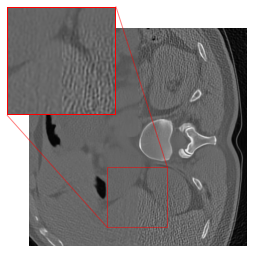

However, our application of this strategy in CT results in artifacts (cf. Figure 1(c)) at the patch boundaries, showcasing a sudden shift from intense to subtle smoothing with the cropping strategy. A reason for this might be that the errors are typically not Gaussian white noise, but more involved. For mitigating the artifacts, we modify the cropping approach of [47] by implementing padding in the output of the FBP to align with the network architecture. The DRUNet architecture operates solely on images sized as multiples of due to its four downsampling steps, whereas the LoDoPaB-CT dataset comprises images of size , which does not conform to this requirement. To address this, we apply mirror padding to enlarge the images to before passing them through the network and subsequently cropping them back to the original size of Figure 2 illustrates the suitability of the proposed strategy. (We point out that the image depicted in Figure 2 represents one of the most challenging reconstructions within the dataset.)

Effectiveness of the Rotational Augmentation

To evaluate the impact of rotational augmentation, we conducted an experiment by training two networks: one with rotational augmentation and the other without. The objective was to investigate the network’s response to input images under different orientations. Specifically, we applied two scenarios: firstly, inputting images as they are, and secondly, rotating them by 90° before feeding them into the networks. Results depicted in Fig. 3 illustrate a noteworthy observation. For the network with rotational augmentation during training (cf. 2(e) and 2(f)), the output remains consistent regardless of the input image’s orientation. However, for the network trained without rotational augmentation (cf. 2(c) and 2(d)), the output varies between the normal and rotated input scenarios. This experiment highlights the effectiveness of rotational augmentation in achieving network equivariance and ensuring consistent performance across different orientations of input images.